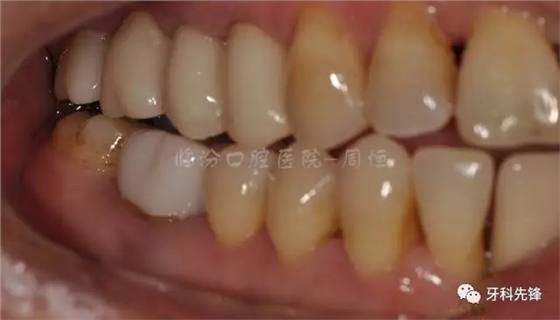

圖2 術(shù)前側(cè)位咬頜照

640.webp (3).jpg